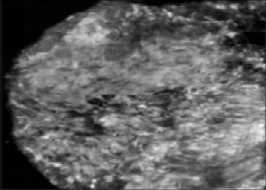

(1)汇聚征(retractionphenomenon):表现为病灶周边放射状分布的条状高回声并向中心汇聚,是冠状面特征表现,对乳腺恶性肿瘤诊断特异度较高。据报道特异度在74%~100%,准确度在85%,阳性预测值达90%[2-4],汇聚征可以仅在部分层面出现,小病灶、较浅及组织学分级较低的侵袭性乳腺癌较易出现,最长径≤2cm病灶汇聚征的阳性率约61%[5]。虽然汇聚征对恶性病变诊断特异度较高,但少部分良性乳腺病变如硬化性腺病、导管内乳头状瘤、放射状疤痕及手术疤痕等也可出现,需要进行鉴别,见图8。

什么是超声容积探头【解读】自动乳腺容积超声技术专家共识 (2022 版)_https://www.jmylbn.com_新闻资讯_第13张

图8 汇聚征

低回声肿块周边呈现向中心汇聚的放射状排列高回声。